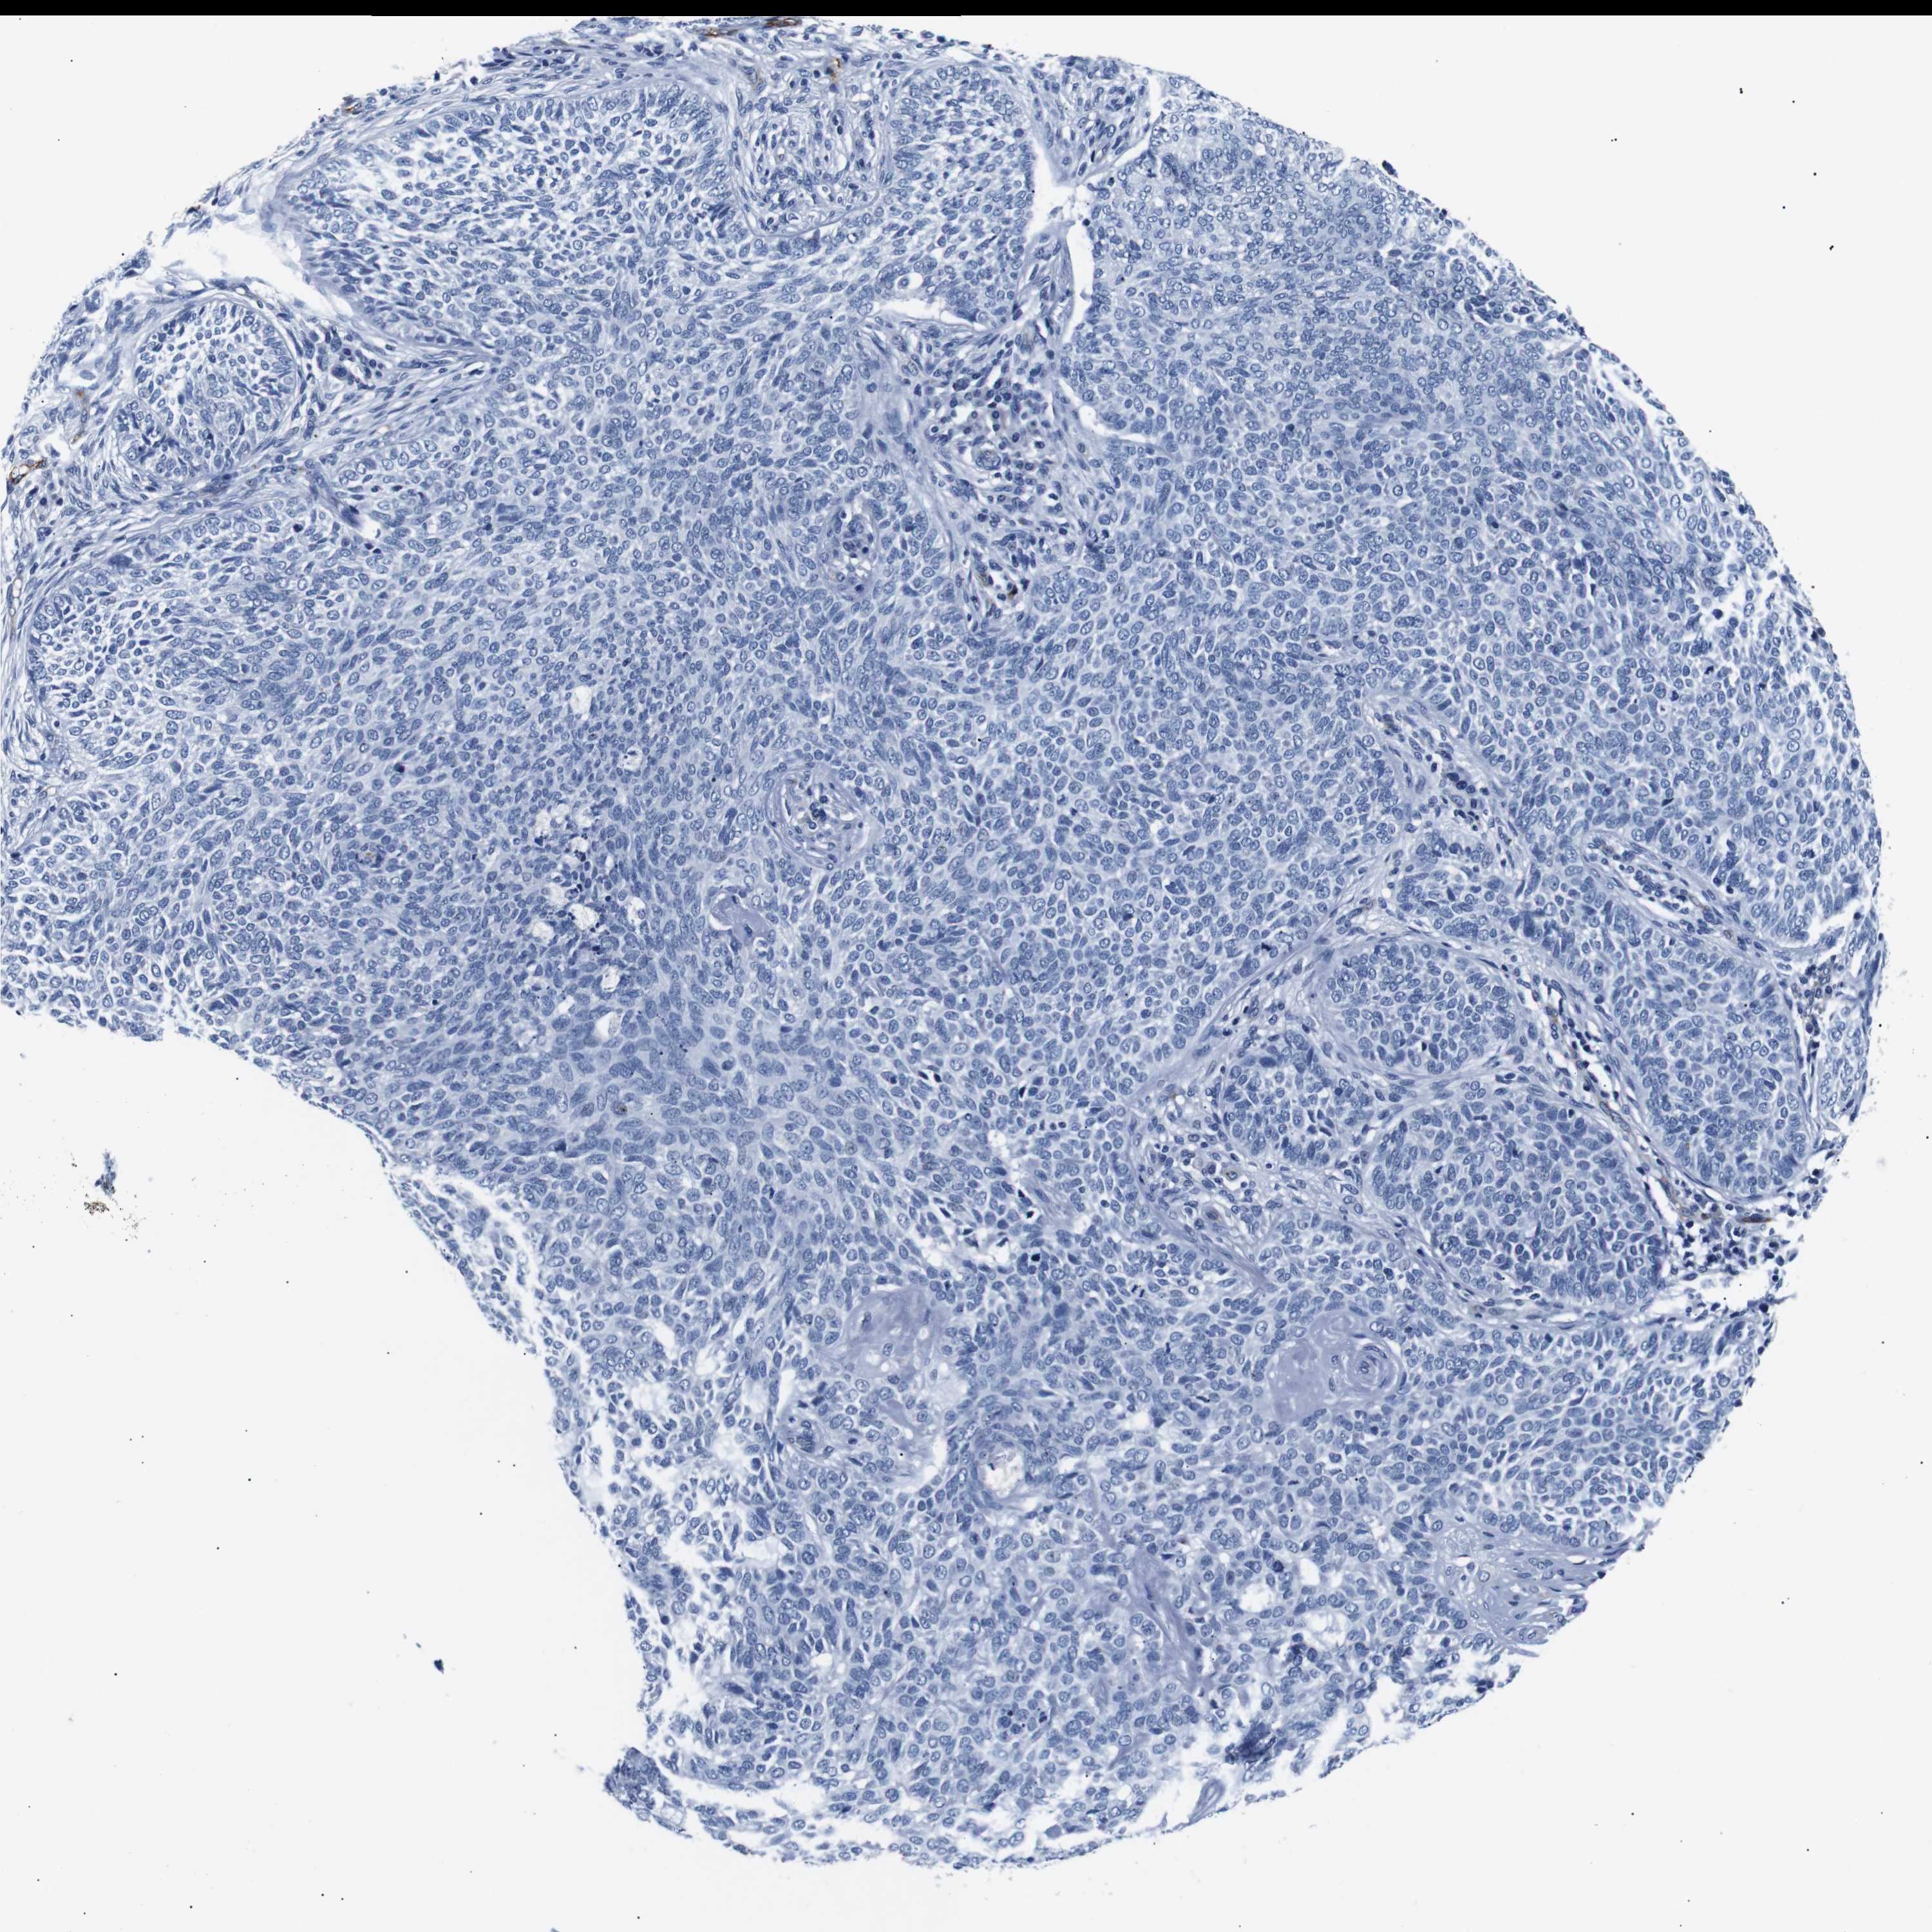

SKIN CANCER - Protein expressioni

A mouse-over function shows sample information and annotation data. Click on an image to view it in a full screen mode. Samples can be filtered based on level of antibody staining by selecting one or several of the following categories: high, medium, low and not detected. The assay and annotation is described here.

Antibody stainingi

Antibody staining in the annotated cell types in the current human tissue is reported as not detected, low, medium, or high, based on conventional immunohistochemistry profiling in selected tissues. This score is based on the combination of the staining intensity and fraction of stained cells.

Each image is clickable and will lead to virtual microscopy that enables deeper exploration of all samples and also displays staining intensity scores, fraction scores and subcellular localization as well as patient and tissue information for each sample.

Antibody HPA005895

Antibody CAB013536

Squamous cell carcinoma, NOS

Basal cell carcinoma